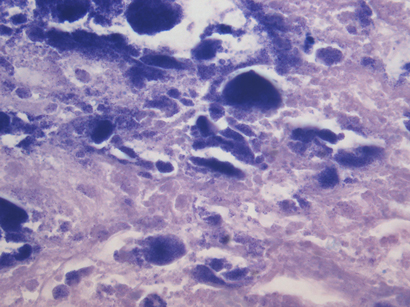

Pathological examination of the specimen showed marked nodular fibrosis and calcification. Preliminary microscopy and cultures of operative specimens revealed no microorganisms. However, transmission electron microscopy of tissue sections confirmed intracellular organisms, in keeping with Coxiella burnetii chronic active endocarditis (Box 3 and Box 4).